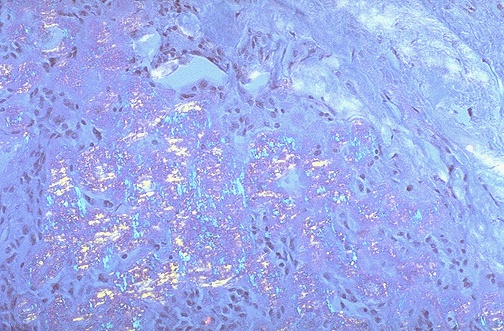

This is the Congo red stained amyloid stroma of the medullary carcinoma under polarized light, which produces a pale greenish appearance.